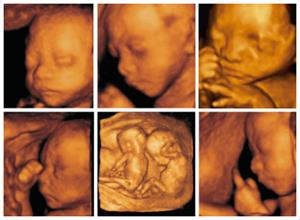

说到四维彩超,其实孕妈妈选择做四维彩超的原因很简单:就是四维彩超能排查畸形,利用四维彩超技术了解宝宝的成长发育情况。相信每一位孕妈妈在孕期对宝宝都有一些担忧,担心宝宝发育有没有问题,对此四维彩超能让孕妈妈了解孕期的一些情况。

这也是做四维彩超的主要目的,除此之外,孕妈妈在做四维彩超的时候,边做检查还可边观看到腹中宝宝的一举一动,还可将此录影留一份纪念,因此很多孕妈妈面对四维彩超检查,都是有点激动的呢。